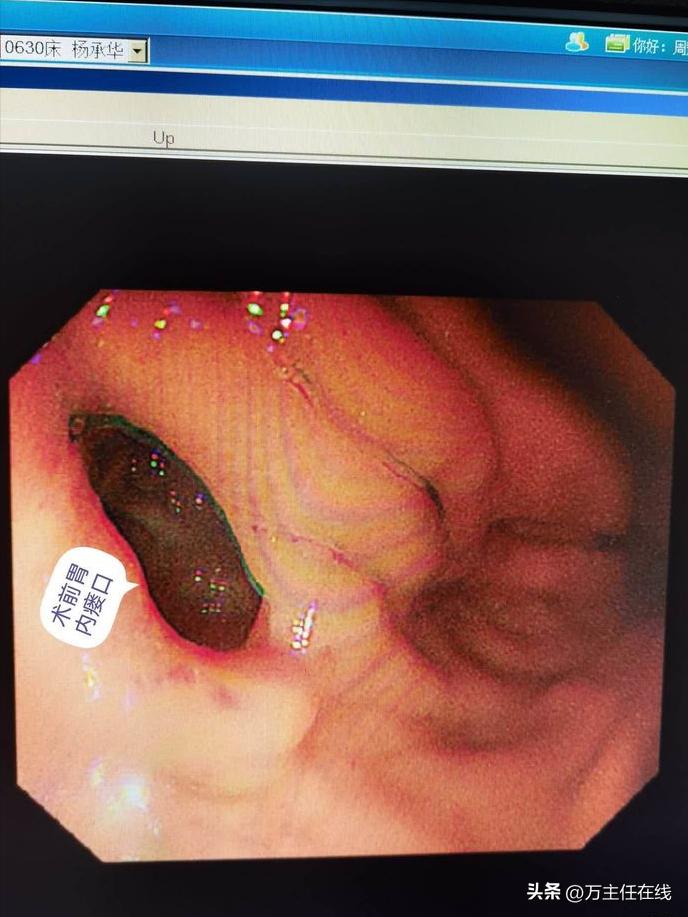

术前内镜探查见胃腔内多发瘘口形成并有少量粘液自腹腔瘘入

胃窦后壁受压,胃腔梗阻;超声内镜引导下胃窦后壁穿刺避开肠管及重要血管留置导丝于腹腔